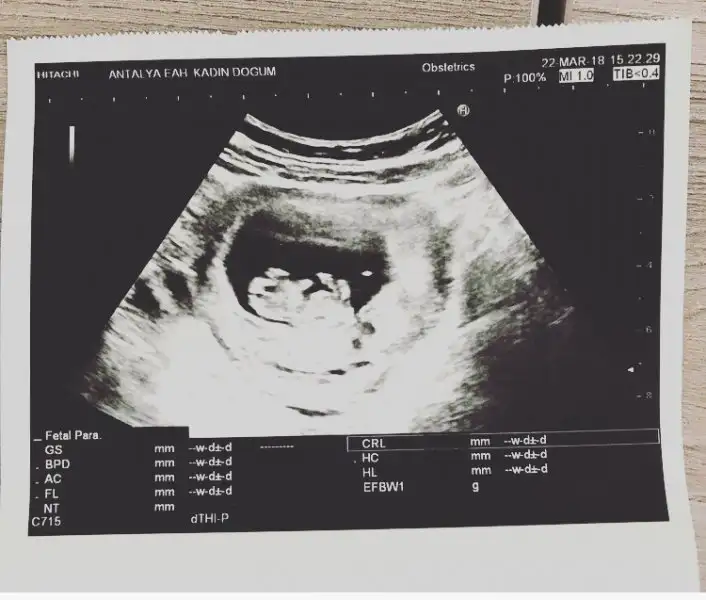

Kızlar cinsiyet tahmininiz var mı bebişim için 9+5 olduk:)

Eklentiler

• C8F90311-8837-4464-9F8B-998FFC0A581F.webp

C8F90311-8837-4464-9F8B-998FFC0A581F.webp

24 KB · Görüntüleme: 84